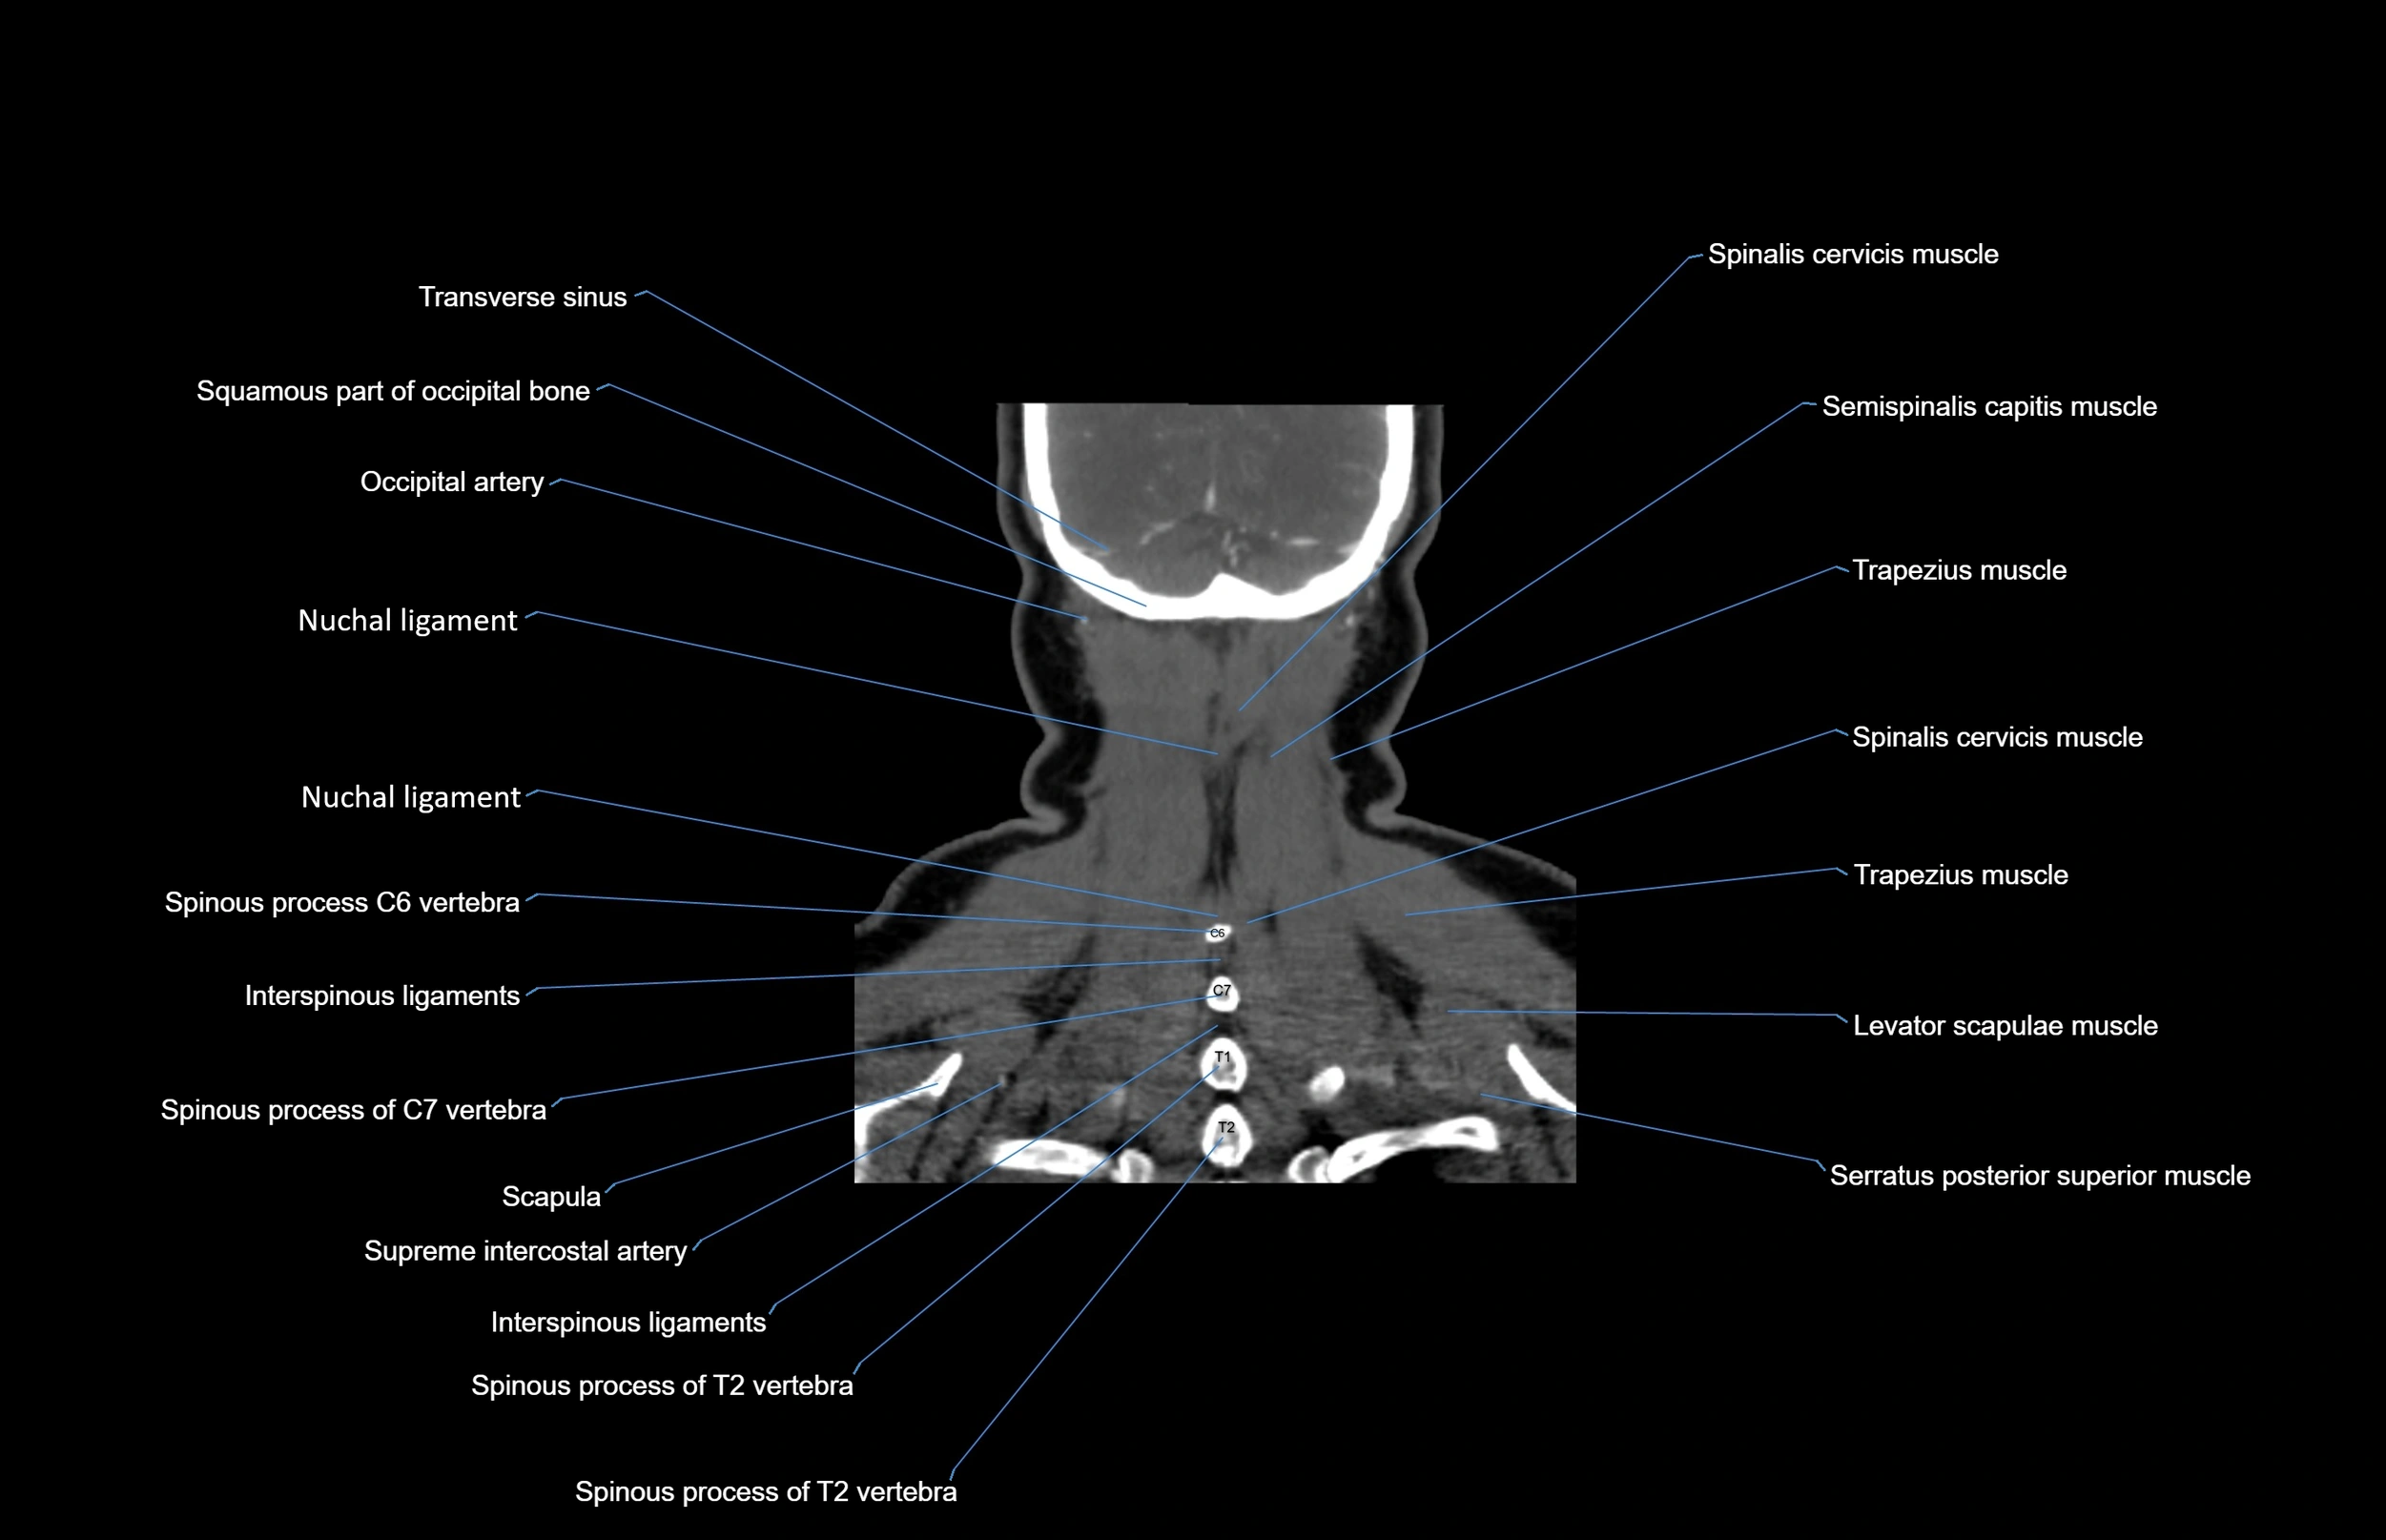

- Multifidus muscles

- Semispinalis capitis muscle

- Semispinalis cervicis muscle

- Spinalis cervicis muscle

- Spinous process of vertebra

- Trapezius muscle